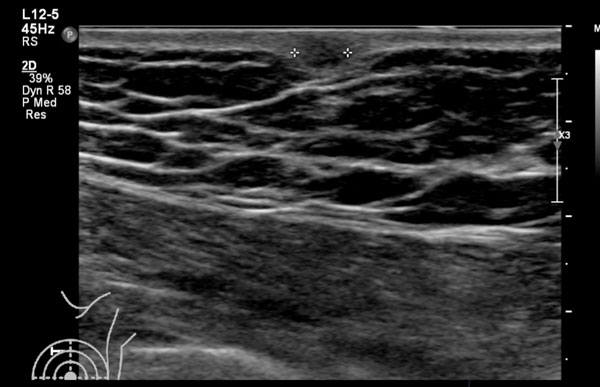

Lưu ý rằng khối ung thư vú nhỏ này được quan sát rõ hơn khi sử dụng chế độ hài âm.

Có một khối giảm âm với quầng tăng âm xung quanh và bóng cản nhẹ phía sau. Hướng của khối u là thẳng đứng.

Bờ khối không rõ và hình dạng khối u không đều.

Đây là một trường hợp khó và không điển hình.

Khi nhìn vào hình ảnh bên trái, gần như không thể nhận ra khối u.

Hình ảnh trông gần giống như mô tuyến bình thường.

Tuy nhiên, trên lâm sàng sờ thấy một khối u, và khi quan sát hình ảnh với chế độ hài âm được bật, chúng ta có thể thấy bóng cản phía sau.

Trường hợp này được xác định là ung thư vú.

Nếu máy siêu âm của bạn có chế độ hài âm, tốt nhất nên quan sát cả hai chế độ có và không có hài âm trong những trường hợp không rõ ràng ngay từ đầu.